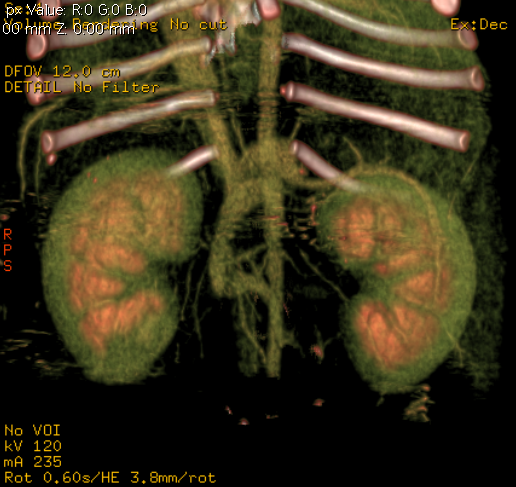

Diagnosis is usually made on the basis of a combination of suggestive serum biochemistry and haematological findings and compatible clinical signs. The diagnosis is confirmed using imaging (usually ultrasound or CT) to identify the abnormal blood vessel. Ultrasound can provide a rapid way to confirm the diagnosis and to visualise the shunt and it can be performed in the conscious patient. CT angiography can also be performed (Fig 1) which is even more sensitive than ultrasound, gives additional information useful to surgical planning but does require a general anaesthetic.

Fig 1: Angiogram of the cranial abdomen showing position of a portocaval shunt